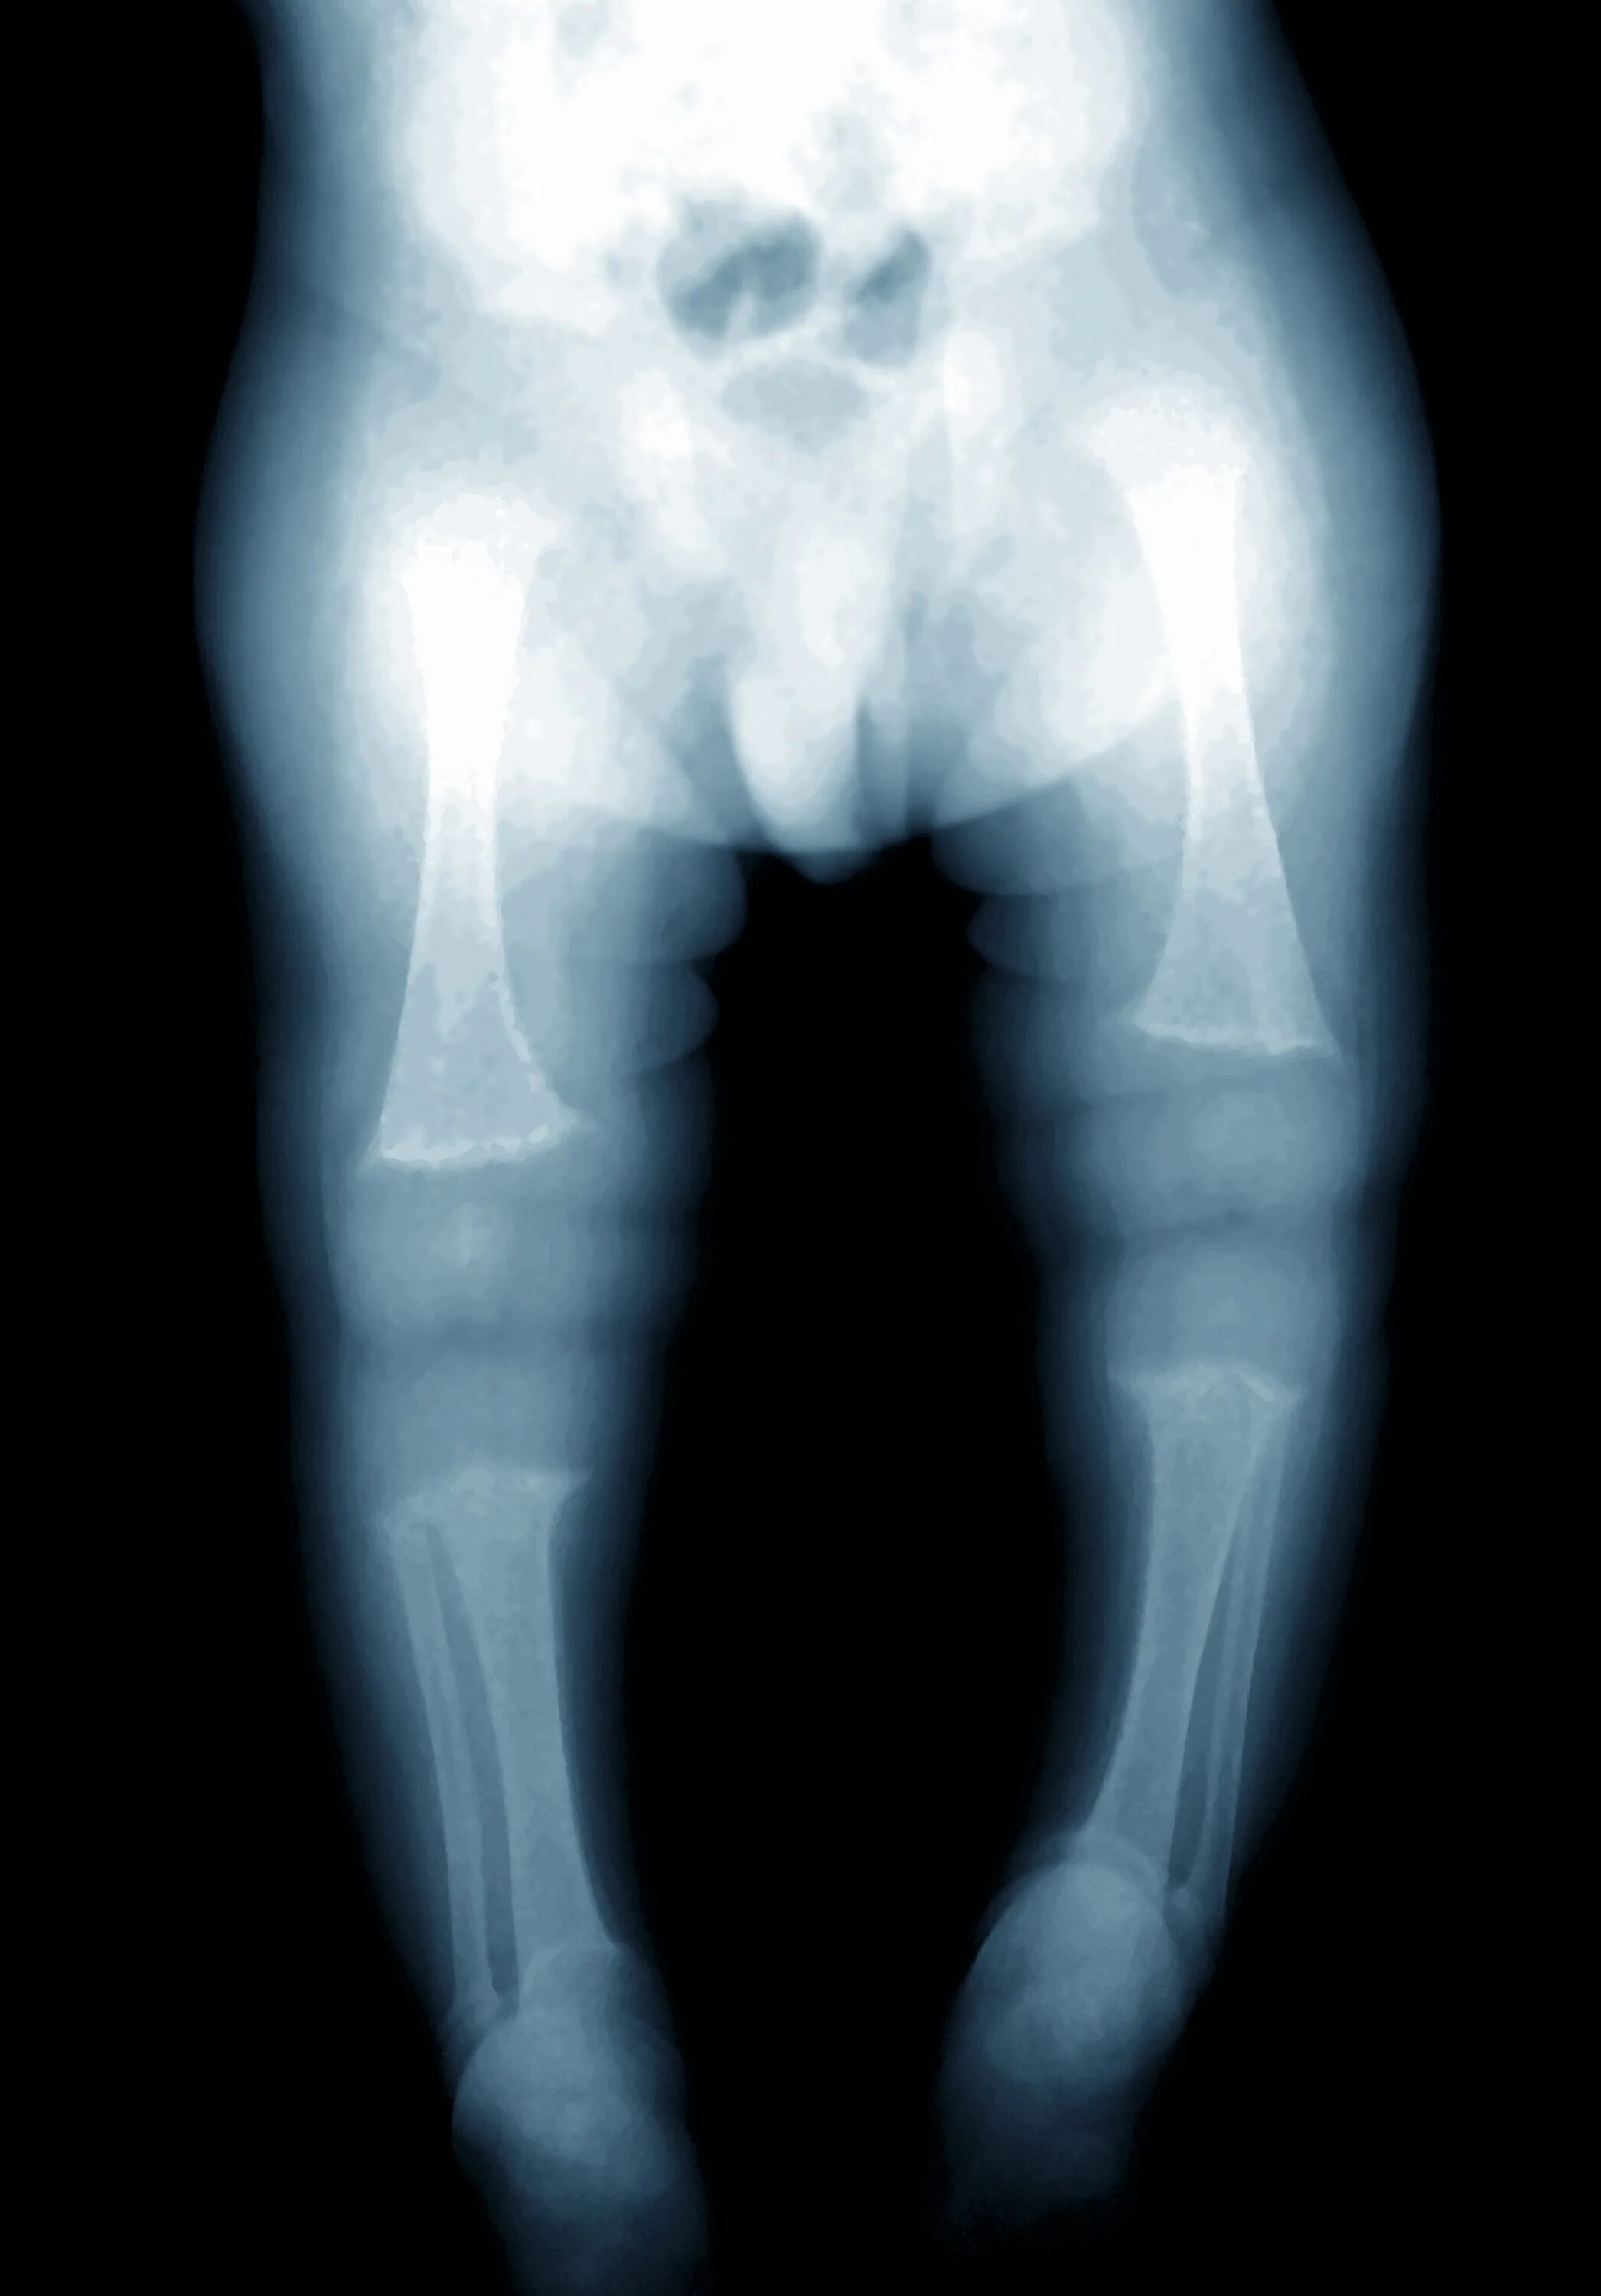

Рахит 6 лет